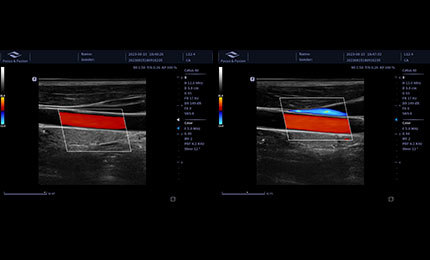

doppler

Obrazowanie tkankowe metodą Dopplera

Technologia Dopplera tkankowego (TDI) umożliwia szczegółową analizę funkcji mięśnia sercowego, w tym prędkości ruchu, przemieszczeń oraz deformacji. Pozwala to na ocenę zarówno globalnej, jak i regionalnej pracy serca oraz synchronizacji jego cyklu.